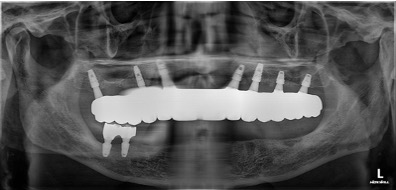

디지털 풀아치 임플란트(상악) & 전체 임플란트(하악) (64세 여성)